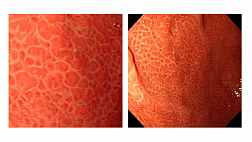

При эндоскопическом исследовании в случае бронхоэктазов в стадии ремиссии выявляется

частично диффузный бронхит I степени воспаления